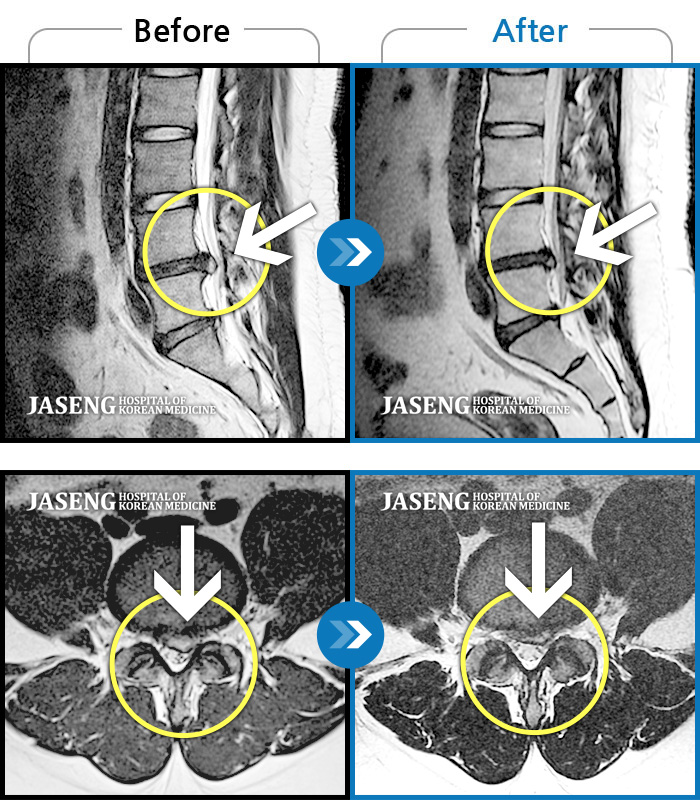

허리디스크

일산 · 김태용 원장

허리와 좌측 하지 방사통이 심하시어 보행이 거의 힘들었다.

촬영시기

2021.03.06 ~ 2021.07.15

2021.07.23